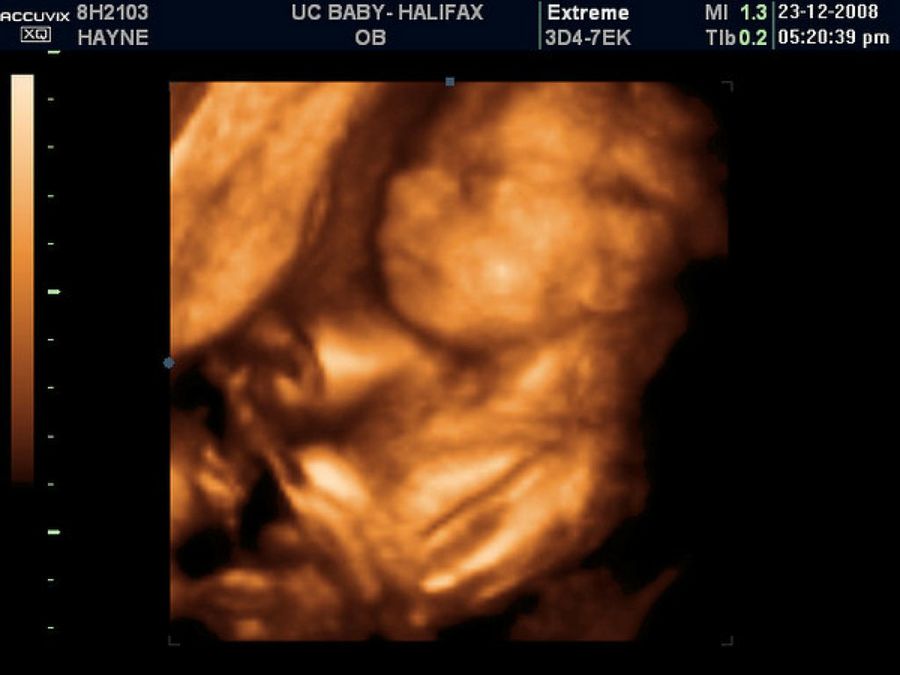

Ecografías

Otro momento clave del embarazo son las ecografías. En los primeros meses apenas se puede percibir algo. Sin embargo, poco a poco el bebé va creciendo y a partir del cuarto mes ya podemos ver el feto con claridad. Además en la decimonovena semana de gestación las futuras ya podrán sentir los movimientos del bebé, momentos que no se olvidan en la vida.En el quinto mes de embarazo llega la ecografía más deseada por muchos padres, se puede saber el sexo del bebé. Es el momento de debatir con la pareja el nombre del futuro bebé, una decisión muy emocionante e importante.Sexto mes